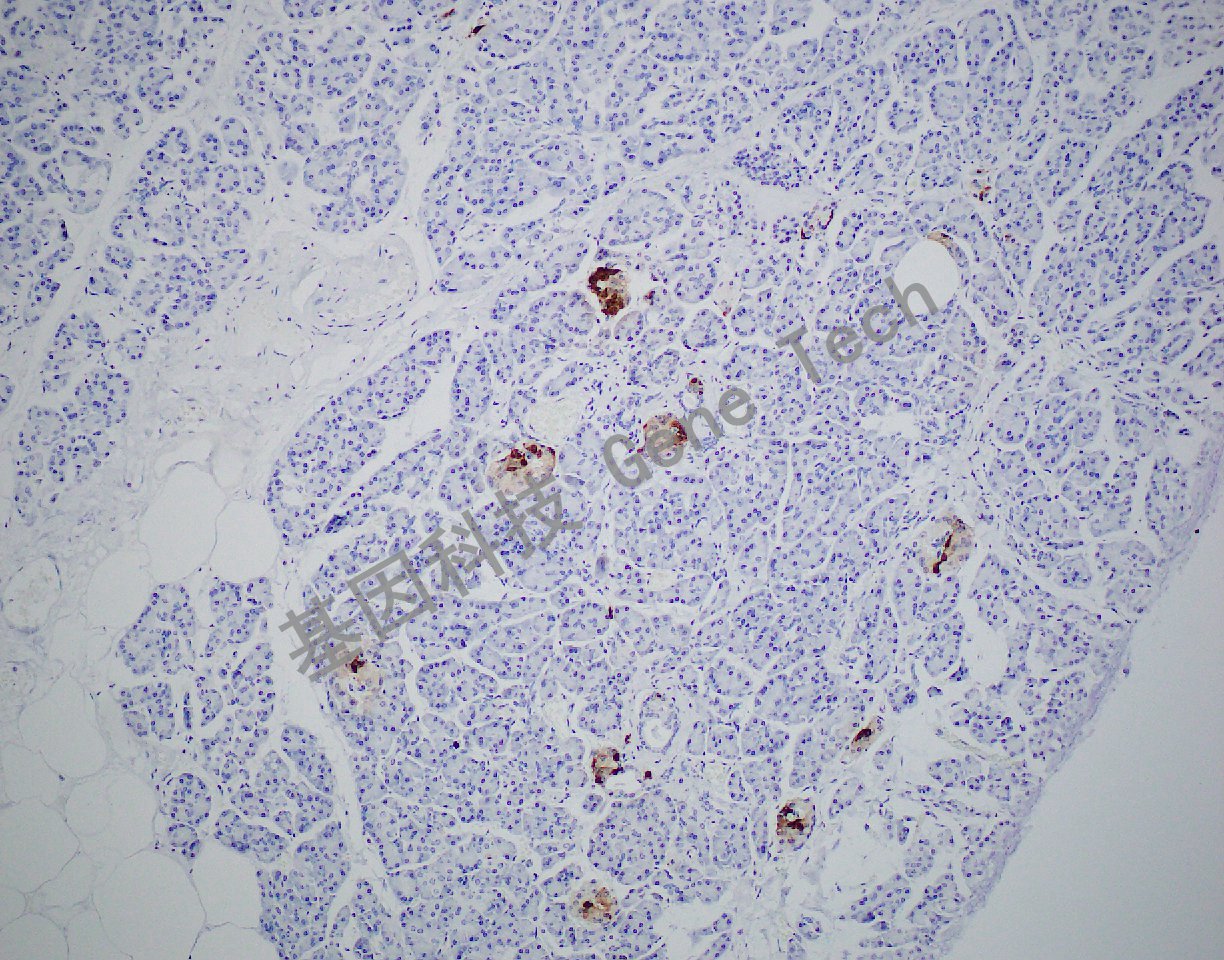

胰腺石蜡切片,用Somatostatin(GA0566)染色,细胞浆阳性,DAB显色。